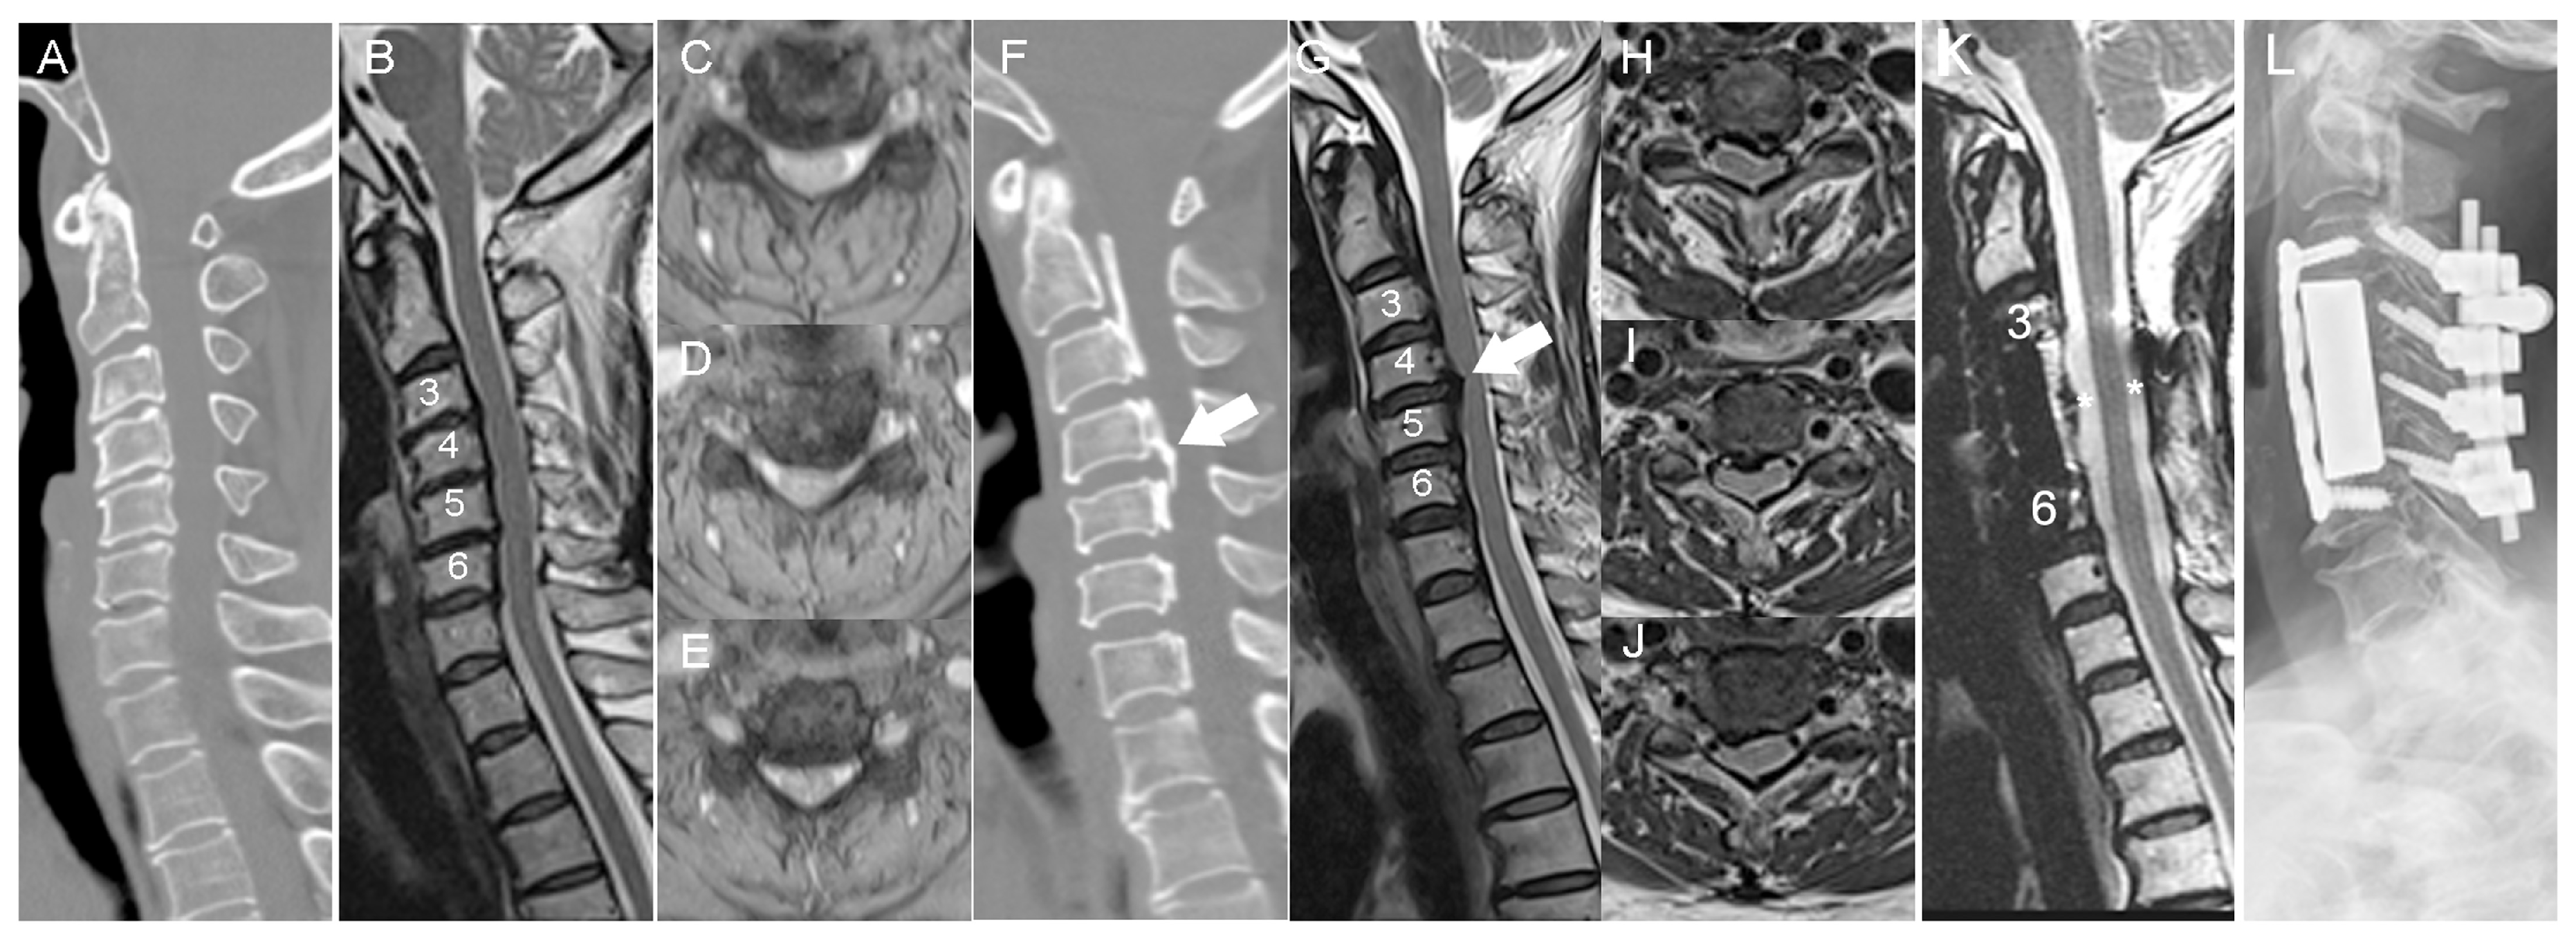

3.1. Patient Demographics

3.2. Histological Staining